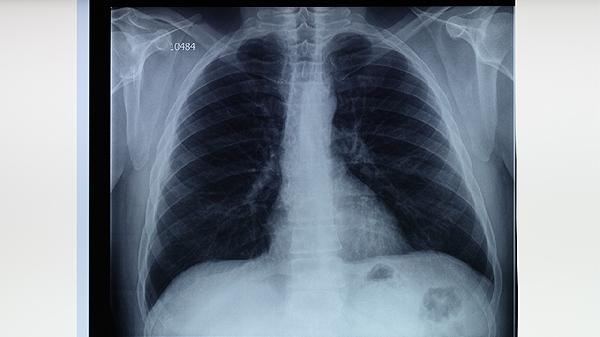

肺結(jié)核患者應(yīng)嚴(yán)格遵醫(yī)囑用藥,不可自行停藥或減量。治療期間要定期復(fù)查胸部影像學(xué)和痰結(jié)核菌檢查。注意個(gè)人衛(wèi)生,避免傳染他人。保持樂(lè)觀心態(tài),保證充足睡眠。戒煙限酒,適當(dāng)進(jìn)行散步等輕度運(yùn)動(dòng)增強(qiáng)體質(zhì)。如出現(xiàn)藥物不良反應(yīng)或癥狀加重,應(yīng)及時(shí)就醫(yī)調(diào)整治療方案。